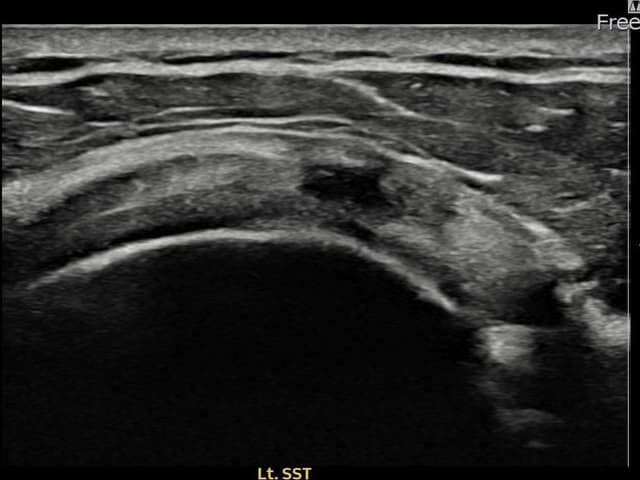

[経過期間: 23.10.23~24.01.04]

[縫縮術] 超音波検査にて左 棘上筋腱 関節面側部分断裂(8mm × 3mm (腱厚の約33%欠損))を確認。縫縮術施行後、腱の連続性が回復し、日常生活に復帰されました。